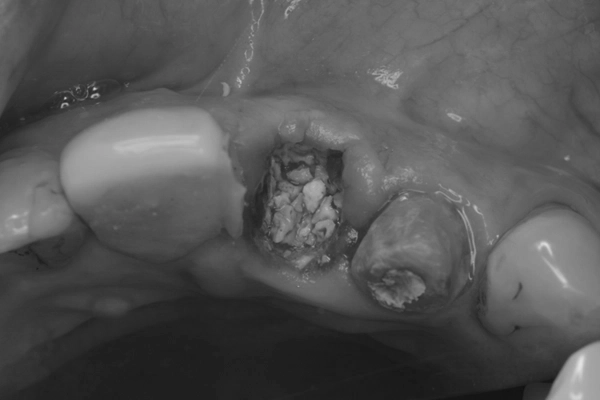

左上1番は抜歯後、抜歯即時は非適応なためリッジプリザベーション(※1)を行い待時埋入を行いました。

リッジプリザベーションの様子

(※1)リッジプリザベーションとは

歯を抜くと、支えていた周囲の骨は役目を終えたと感じて自然に痩せていってしまいます。これを防ぐための処置がリッジプリザベーションです。

抜歯した直後の穴に「骨を補う材料」を詰め、骨の吸収を最小限に抑えます。あらかじめ骨のボリュームを維持しておくことで、その後のインプラント治療をより安全・確実に、かつ見た目も美しく仕上げることが可能になります。